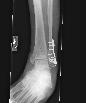

Dr. Visit 8-8-07 - The infection is healing and x-rays show most of the fracture has filled in. Look mid plate and to the left on x-ray #3 to see what is left of the fracture.